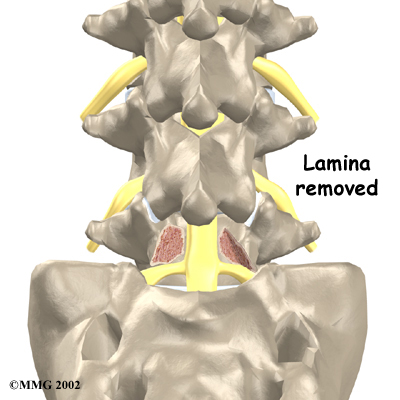

- laminectomy (decompression)

Laminectomy

When the vertebra slips forward, the nearby nerves that exit the spine can become pinched or irritated. In addition, the size of the spinal canal in the problem area shrinks, placing pressure on the nerves inside the canal. To fix this, the lamina of the bony ring is removed to ease pressure on the nerves. The procedure to remove the lamina and release pressure on the nerves is called . Decompression alone is usually not advised. Studies show much better results when the operation is combined with a fusion of the involved vertebrae (see below).

Related Document: Iron City Physical Therapy's Patient's Guide to Lumbar Laminectomy